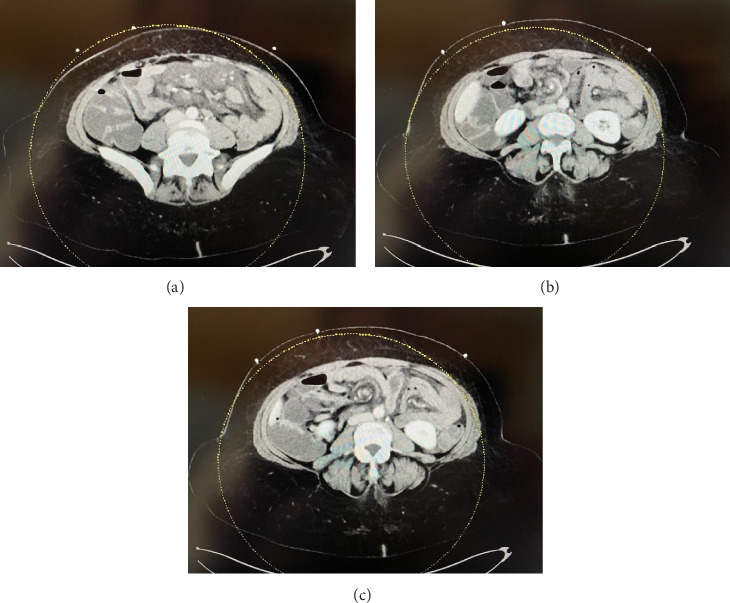

小肠梗阻引起的乳糜腹水是一种非常罕见的发现,以前只发表过少数病例报告。本病例报告的患者乳糜腹水相关的梗阻从彼得森疝支持现有的趋势报告。先前的研究已将乳糜腹水与小肠扭转或内疝等闭环阻塞联系起来,即使肠道存活且不需要切除。

Chylous ascites from small bowel obstructions is a very rare finding with only a handful of case reports previously published. This case report of a patient with chylous ascites related to an obstruction from Petersen's hernia supports the trend from existing reports. Prior studies have linked chylous ascites to closed-loop obstructions, such as small bowel volvulus or internal hernia, even when the bowel is viable and does not require resection.